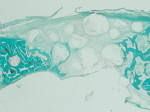

The GUIDOR easy-graft granules are openly microporous. Macropores exist in the spaces between the round, pressure-resistant granules and the interior of the particles (Figure 5 through Figure 7). The total porosity is approximately 70%. In this development of bone graft substitutes, attention was paid to ensuring that the material would not fragment or crumble during application to make sure that a comprehensive, intact pore system is retained. Figure 8 shows bone formation around the granules in a rabbit cranial model after 16 weeks.15